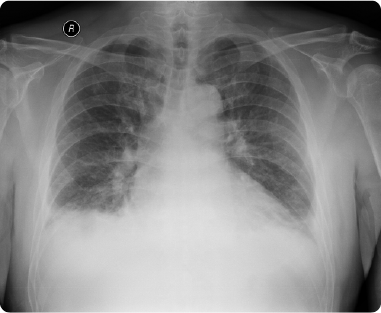

「心不全とは、心臓が悪いために息切れやむくみが起こり、だんだん悪化し、生命を縮める病気」(日本循環器学会 急性・慢性心不全診療ガイドライン2017年改訂版)と定義されています。このように、心不全というのは単一の病気の名前ではなく、あらゆる心疾患の終末像であるととらえることができます。

心不全は、もともと高齢者に非常に多く見られる病気であり、日本では今後さらに急速に高齢化が進むことから、心不全患者さんの著しい増加(心不全パンデミック)が予想されています。 当院では、心不全の症状が出現する前からの予防医療にも積極的に取り組んでいます。また、看護師、理学療法士、薬剤師、管理栄養士、MSW(メディカルソーシャルワーカー)などとチームを組んで、心不全チームとしてきめ細やかなケアを心がけています。

心不全の胸部X線画像